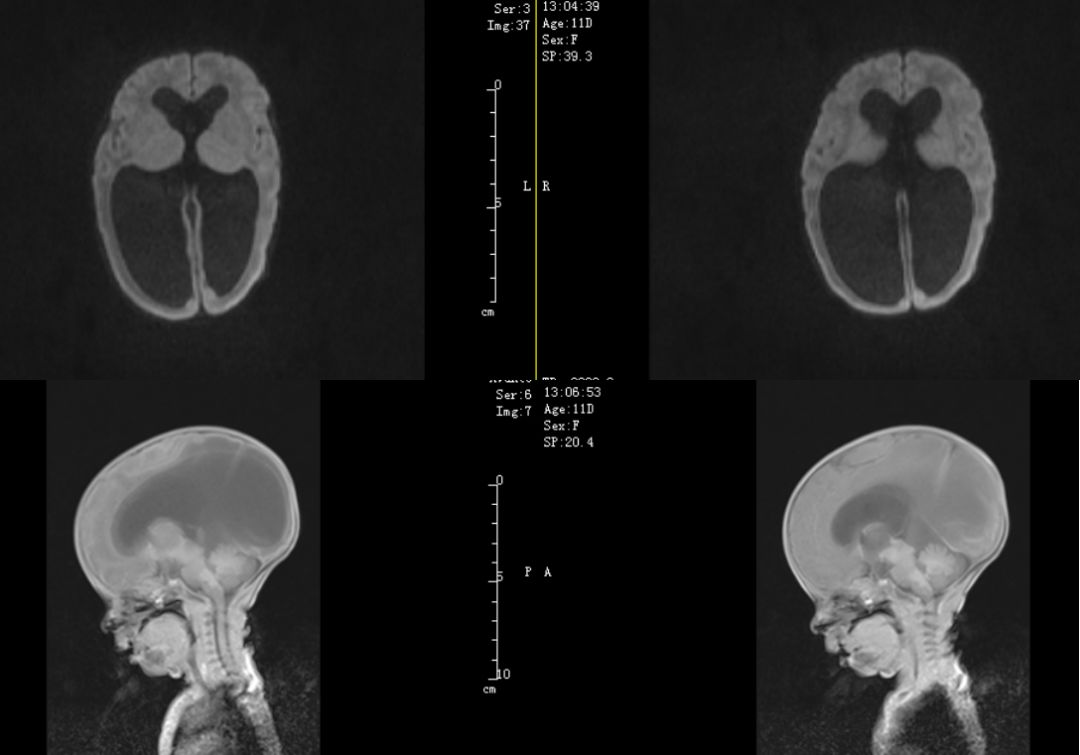

病例2,头颅CT及MRI检查,结果与病例1类似。

科室讨论:两例患儿为弃婴双胞胎,出生史胎龄不详,低体重儿,仅1560g和1410g,B超发现脑室扩大,腰穿结果均为淡黄色,无明显感染迹象,CT和MR提示重度脑积水,导水管以上脑室扩张明显,四脑室正常,未见明显占位病变,考虑先天性发育畸形引起的中脑导水管狭窄,不排除新生儿脑室内出血后继发性导水管梗阻或狭窄可能,建议动态观察头围变化和监测B超,间断行腰穿释放脑脊液降低颅内压,有进行性加重可考虑手术干预。